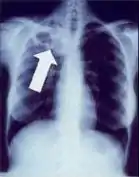

Radiology (X-rays) is used in the diagnosis of tuberculosis. Abnormalities on chest radiographs may be suggestive of, but are never diagnostic of TB, but can be used to rule out pulmonary TB.

Tuberculosis creates cavities visible in x-rays like this one in the patient's right upper lobe.

A posterior-anterior (PA) chest X-ray is the standard view used; other views (lateral or lordotic) or CT scans may be necessary.

In active pulmonary TB, infiltrates or consolidations and/or cavities are often seen in the upper lungs with or without mediastinal or hilar lymphadenopathy.[1] However, lesions may appear anywhere in the lungs. In HIV and other immunosuppressed persons, any abnormality may indicate TB or the chest X-ray may even appear entirely normal.[1]